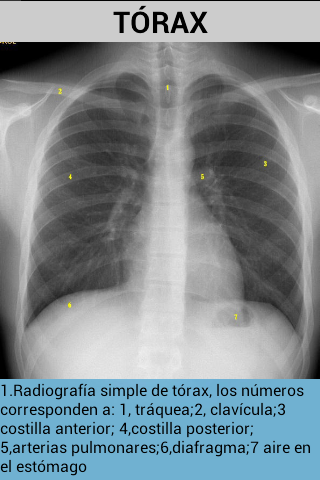

Tato aplikace se naučí snadno identifikovat anatomické struktury, které lze vidět v radiologii.obsahuje obrázky prostých rentgenových snímků, MRI a CT skenů.

Také s každým obrázkem je vysvětlení, které lépe porozumí.

obsahuje obrázky hlavy, páteře a hrudníku.